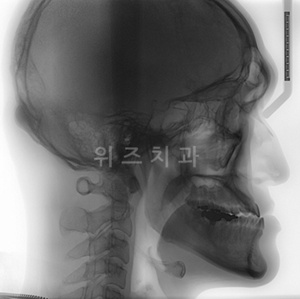

주걱턱은 아래턱이 과 성장하면서 아랫니가 윗니를 덮게 되는 3급 부정교합에 속한다. 통계에 따르면 우리나라 국민의 15-17%가 다양한 양상의 주걱턱을 가지고 있다. 주걱턱, 안면비대칭, 돌출입, 무턱 등 다양한 턱변형 중에서 주걱턱이 가장 많은 비율을 차지한다.

여기에, 주걱턱과 같은 턱 변형을 호소하는 경우에는 안면비대칭이 동반되는 경우가 적지 않다. 턱의 변형은 입체적으로 나타나기 때문이다. 치과 구강악안면외과(구강외과)의 턱수술치료법인 양악수술은 주걱턱과 안면비대칭, 돌출입, 무턱 등 어떠한 턱의 변형도 동시에 개선할 수 있다.

턱의 잘못된 성장으로 인한 주걱턱, 안면비대칭 등은 치아교정으로는 개선이 어렵다. 위 아래 치아의 관계를 개선하더라도 잘못된 턱의 크기와 위치는 그대로이기 때문에 주걱턱의 안모는 고스란히 남는다. 때문에 성장기 이후에 주걱턱의 안모를 교정하는 방법은 양악수술과 같은 턱교정 수술이 유일하다. 턱변형의 상태에 따라 필요한 수술의 내용이 달라진다. 같은 진단명이라도 복합적으로 나타나는 변형이 다양하기 때문에 적절한 진단과 함께 입체적인 변화를 포함하는 체계적인 계획하에 수술을 받아야 확실한 안모의 개선이 이루어질 수 있다.

위즈치과 김기정 원장은 “턱교정 수술 후 드러나는 안모의 개선과 조화를 위해서는 얼굴의 비율을 고려하는 과정이 필수적” 이라면서 “얼굴의 전체적인 균형을 되찾는다는 의미는 기능과 외모 모두가 개선되는 것을 의미하기도 한다”고 말했다. 수술이 얼굴 전체 비율에 미칠 영향을 충분히 고려하여 수술하여야 균형 잡힌 매력적인 얼굴이 될 수 있으며 턱의 기능 회복과 동시에 외모의 개선을 충족시켜야 한다는 것이다. 기능과 외모를 모두 개선하기 위해서는 이 두 가지 목적을 위한 계획과 수술이 같은 병원에서 수술을 담당할 집도의에 의해 직접 진행되는 것이 중요하다.

턱교정 수술에서는 기능과 외모의 개선을 조화시키는 것이 무엇보다 중요하기 때문에 기능의 회복을 위해서는 정교한 수술 계획과 이것을 정확히 옮기는 수술 실력이 바탕이 되어야 한다.